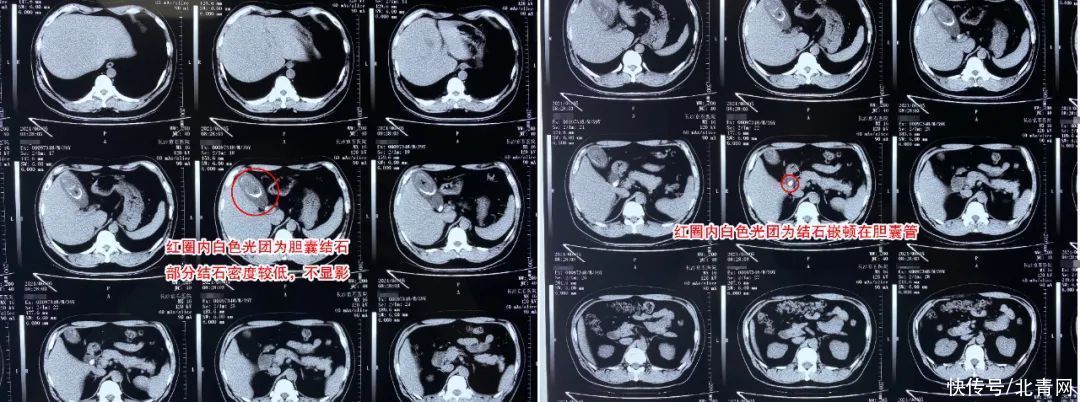

秦先生术前检查CT局部图术中发现胆囊壁已无弹性遗憾切除无功能胆囊6月4日,秦先生在办理完入院手续之后,接受了详细的术前检查,确诊患有胆囊多发结石、并慢性胆囊炎,较为危险的是胆囊管里已有结石梗阻,胆囊是否功能正常,还需术中仔细评估。

6月8日,经过数日的抗炎补液治疗,秦先生的身体状况已达到手术标准。医生团队为秦先生顺利施术,遗憾的是术中发现胆囊已无功能,只能遗憾切除。据长沙京石结石医院肝胆外科主治医师欧涛介绍:“手术中我们发现,他的胆囊被结石填满了,几乎没有胆汁,整个胆囊壁都已经失去弹性,没有功能了。像这样的胆囊没有保留的意义,因此在征得家属同意后,术中及时转为切胆手术。”